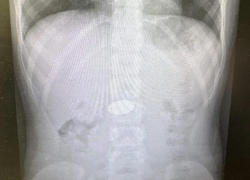

У жительницы Средней Ахтубы вовремя выявили диабет и рак груди

Регулярная диспансеризация доказала свою эффективность. В Среднеахтубинском районе благодаря своевременному обследованию у пациентки 1969 года рождения удалось ...